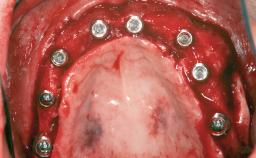

# of Teeth 14

# of Implants 12

Type of Implants One-Piece|Reduced-Diameter

Bone Augmentation Horizontal|Staged

Augmentation Materials Autogenous chips|Autogenous block(s)|Membrane